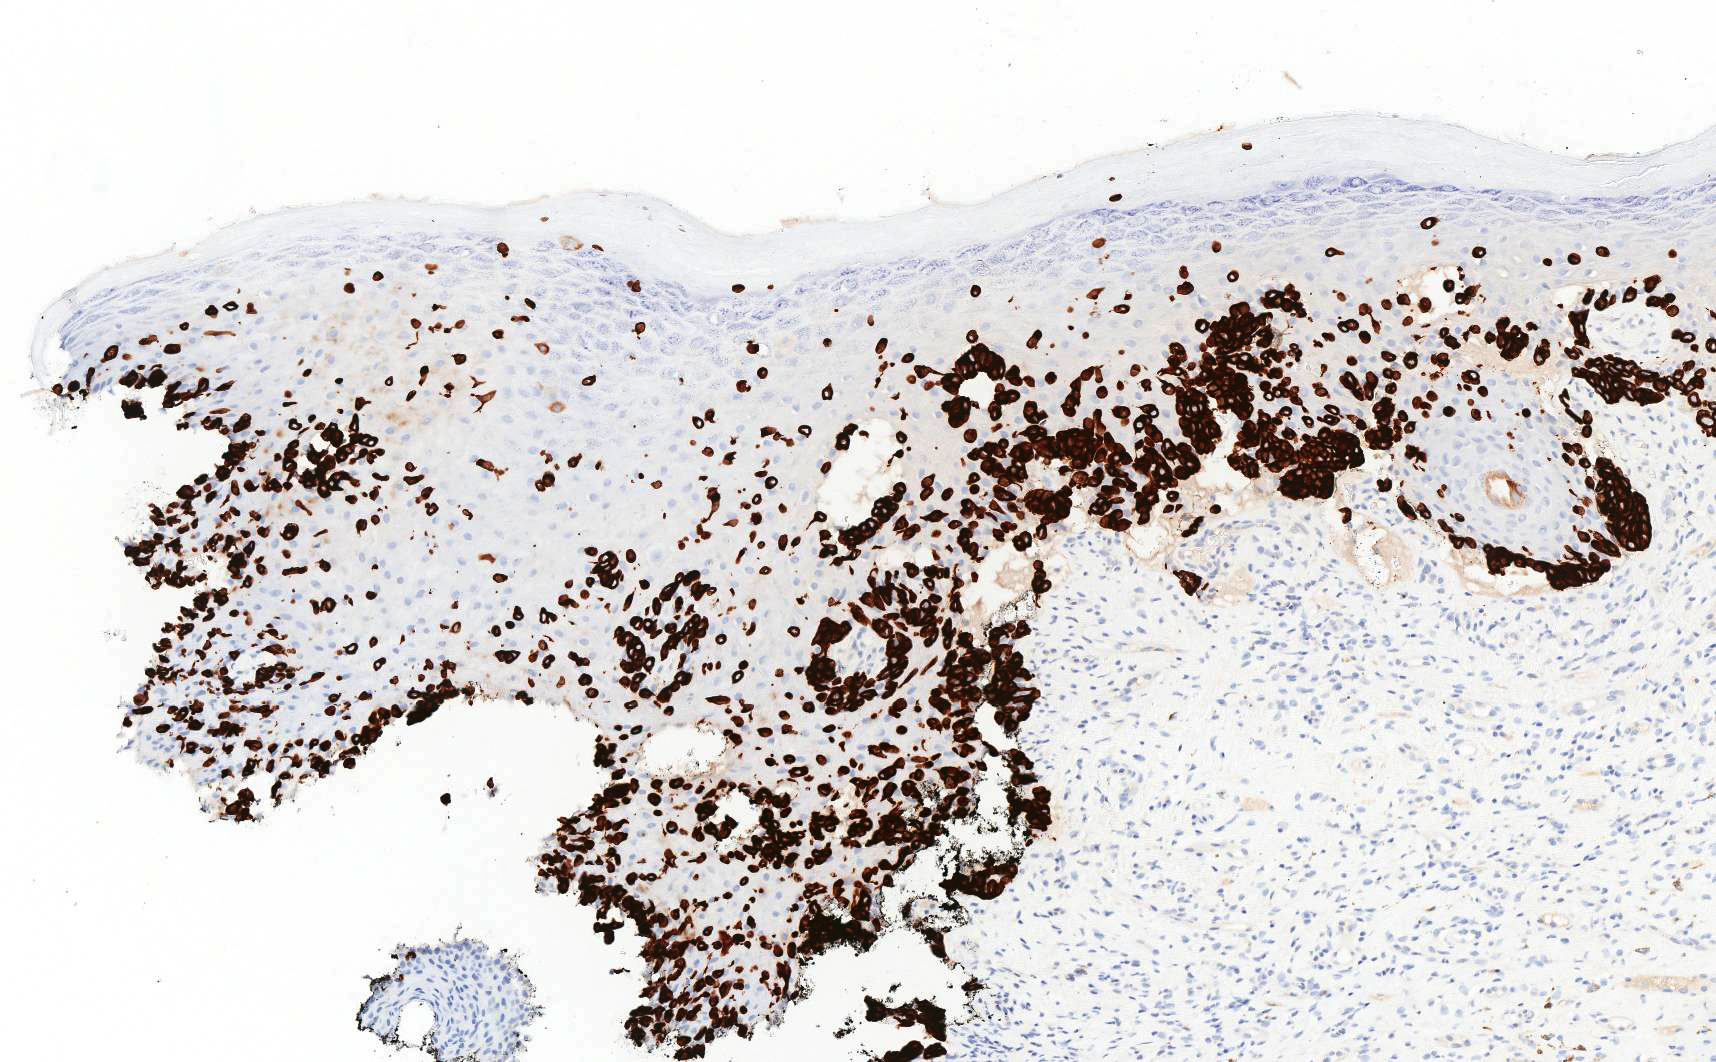

- In primary Paget disease, neoplastic cells are consistently strongly positive for CK7

Microscopic (histologic) images

Contributed by Priya Nagarajan, M.D., Ph.D. and Lucy Ma, M.D.

Positive stains

- Primary and secondary Paget disease: CAM 5.2, EMA, CEA, mucicarmine, periodic acid-Schiff (PAS)

- Primary Paget disease: CK7, GATA3, GCDFP-15, androgen receptor, p16 (weak to moderate) (Am J Clin Pathol 2000;113:572)

- Comment: On immunostains, the neoplastic cells are strongly positive for CK7 and CAM 5.2 and negative for SOX10, supporting the diagnosis.